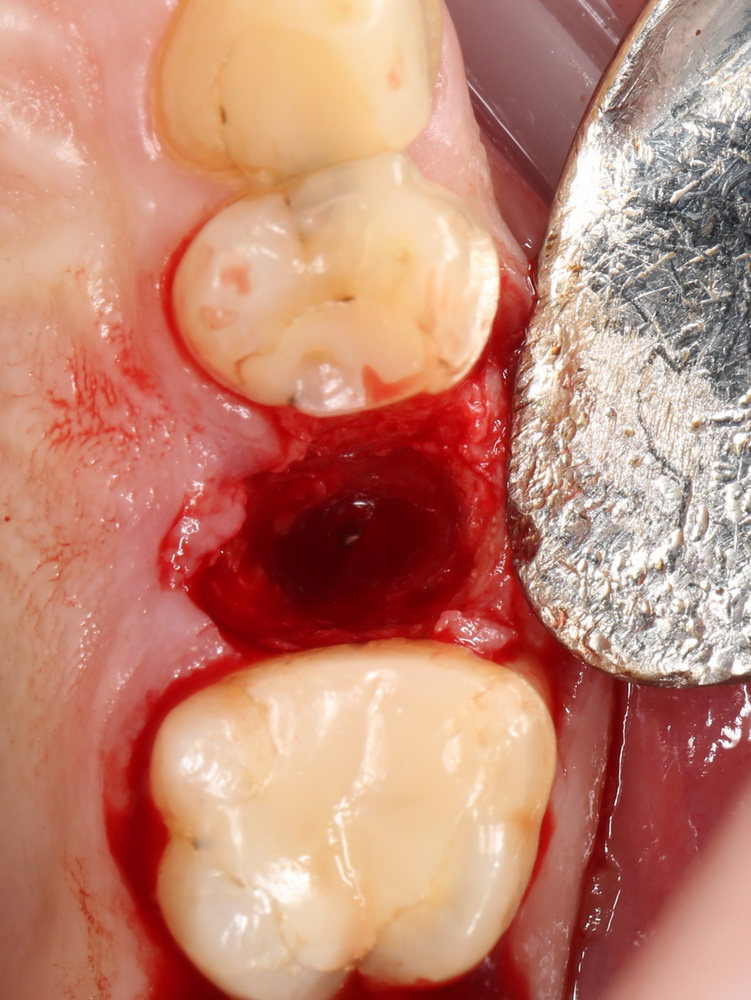

Давайте внимательно посмотрим на состояние лунок центральных резцов после удаления:

Приемлемый фенотип (сочетание толщины и ширины участка жевательной десны) — это, конечно, приятно. Но гораздо важнее сосредоточиться на рисках, их на этот момент два:

— травматическое повреждение слизистой, вызванное удаление зубов связано с тем, что при хроническом воспалении слизистая оболочка теряет эластичность, поэтому легко рвётся. Такая ситуация создаёт серьёзную угрозу эстетическому результату лечения, в зависимости от того, насколько быстро десна придёт в норму.

— как и предполагалось после КЛКТ, утрата костной стенки привела к тому, что десна провалилась в просвет лунки левого центрального резца. Это еще больше усугубляет клиническую ситуацию.